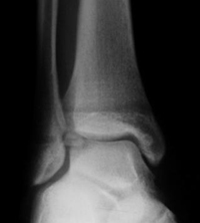

Es una lesión que afecta el hueso y el cartílago de cualquier superficie articular. Anteriormente se conocía como osteocondritis disecante. Esta lesión altera el funcionamiento normal de las articulaciones y puede producir dolor. El tobillo es una de las articulaciones que más se afecta.

Las causas principales de las lesiones osteocondrales de tobillo son los traumatismos y las alteraciones vasculares. El primer consejo que damos a nuestros pacientes es realizar descarga, controlar la sobrecarga ponderal, antinflamatorios no esteroideos (AINE) y utilizar plantillas si existe alguna alteración estructural.

El tratamiento dependerá del tamaño y localización de la lesión. La técnica más utilizada para tratar estas lesiones son las microfracturas y perforaciones realizadas con artroscopia. Cuando la artroscopia ha sido inefectiva o la lesión es muy grande, será necesario utilizar injertos, matriz cartilaginosa o cultivos de condrocitos. Nuestro equipo le aconsejará la operación que mejor se adapta a sus necesidades.